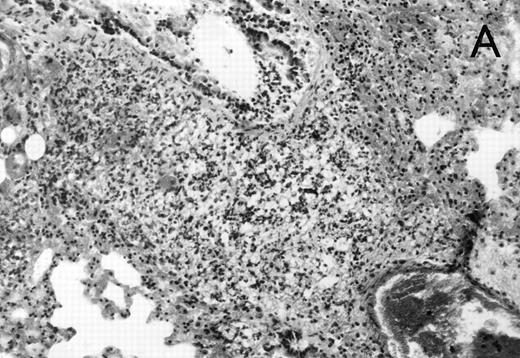

Histology further supported this observation. Control animals showed well-developed pneumonia with abscess formation (Fig3A) in their lungs, but in their livers, only small areas of inflammation with scattered microabscesses and foci of hepatic necrosis were observed (Fig 3B). In contrast, mice pretreated with G-CSF had only mild peribronchitic alterations in their lungs without signs of containment of inflammation such as abscess formation (Fig 4A). Livers and spleens of mice pretreated with G-CSF were severely altered, showing large abscesses which contained massive amounts of bacteria (Fig 4B). In addition, large necrotic areas surrounded by granulocytes were observed in the livers (Fig 4C). When MoAb III/5-1 was administered in addition to pretreatment with G-CSF, almost all changes observed in animals pretreated with G-CSF were reversed: there were only minor bronchial and peribronchial infiltrations by granulocytes (minimal change focal pneumonia), and the livers showed small microabscesses as observed in control mice. When treatment with G-CSF was started at 24 hours after bacterial challenge, a mixed pattern was observed. In the lungs, there was a beginning pneumonic reaction and a moderate perivascular and septal edema. However, in the liver there was almost no difference to the severe alterations observed in mice pretreated with G-CSF: huge abscesses loaded with bacteria joined extended necrotic areas.

(A) Micrograph of lung tissue 72 hours after intranasal infection with 1 × 103 CFU of K pneumoniae B5055. Lung abscess with severe tissue destruction in a PBS-treated control animal. Hematoxylin & Eosin (H&E); original magnification ×150. (B) Small foci of hepatic necrosis. H&E; original magnification ×600.